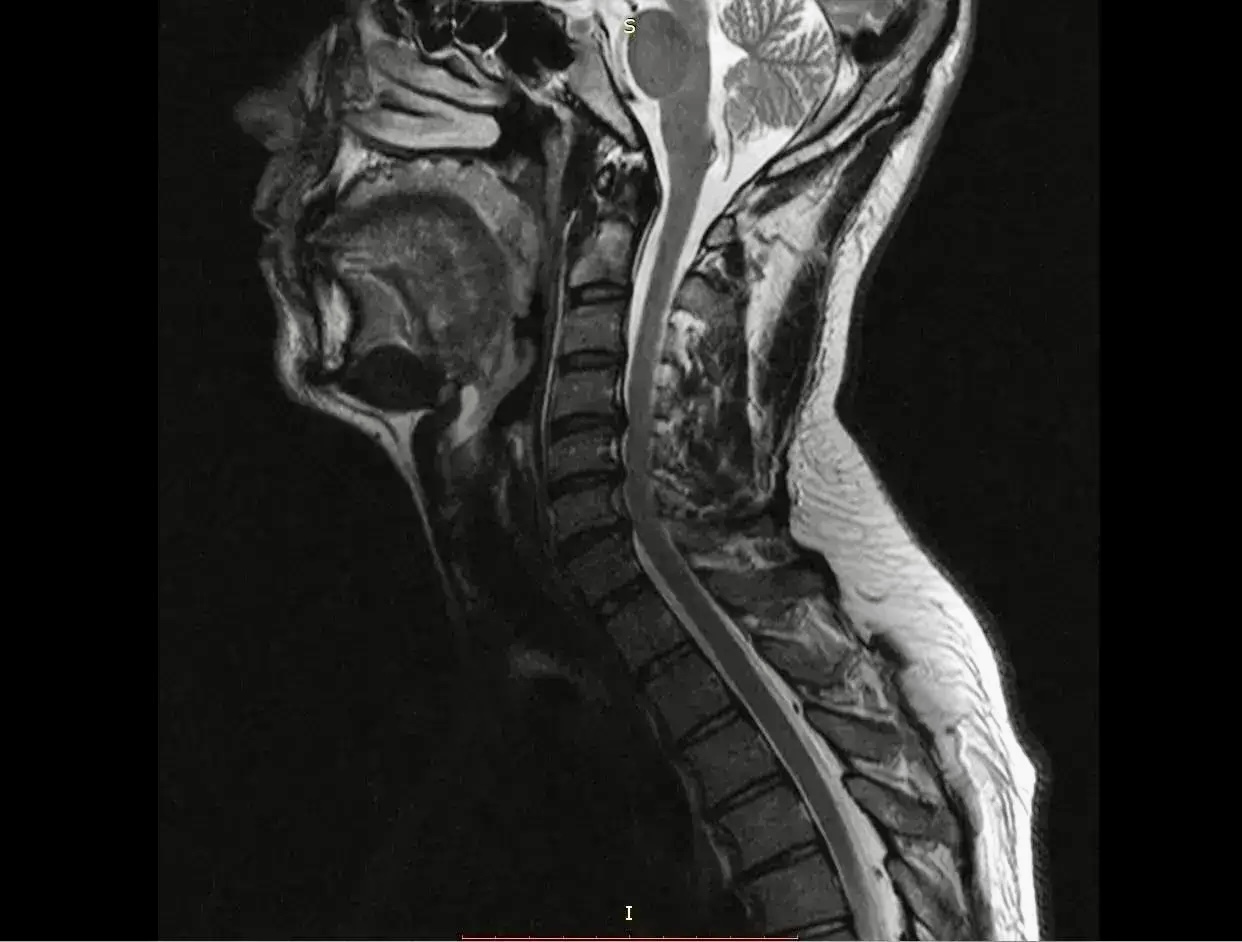

Пациента госпитализировали в плановом порядке, так как консервативное лечение не дало эффекта. В стационаре ему диагностировали диско-остеофитный стеноз позвоночного канала на уровнях C3-C4, C4-C5, C5-C6 и C6-C7. Это состояние связано с сужением позвоночного канала и сдавлением находящихся в нем структур.